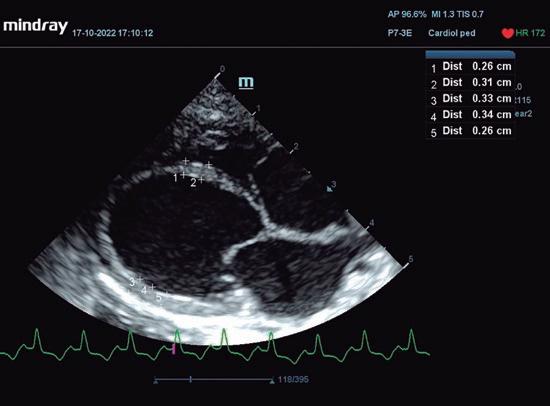

• Modo B: en la proyección paraesternal derecha eje largo, se observó un jet de regurgitación mitral con dirección posterior y SAM (figura 3). En el eje corto derecho a la altura de la base cardiaca se observó un ratio atrio izquierdo/aorta (AI/Ao) de 1,92 (>1,6 se considera dilatación AI) (figura 4). Además, se observó hipertrofia de la pared del septo interventricular (SIV) de 7,6 mm y la pared libre del ventrículo izquierdo (PLVI) la 8,4 mm (hipertrofia >6 mm) (figura 5).

Ecocardiográficamente se observa un aumento de cámaras cardiacas izquierdas2,3, paredes ventriculares que pueden presentar adelgazamiento2,5 (figura 2), disminución de la función sistólica ventricular, y de la fracción de acortamiento3, con aumento de la distancia del punto E al septo.2,5

En la ecocardiografía se advierte un aumento del tamaño de cámaras cardiacas derechas (figura 4) y regurgitación tricúspide evidenciada con Doppler color. El movimiento de la pared libre del ventrículo derecho puede estar reducido en algunos gatos, mientras que el del septo interventricular puede ser paradójico. La cavidad del ventrículo izquierdo puede ser normal o estar disminuida, aunque la aurícula izquierda puede estar aumentada en algunos gatos.3

Además, al evaluar cualquier fenotipo de cardiomiopatías hay factores independientes que nos indican un riesgo elevado de insuficiencia cardiaca congestiva (ICC), como el aumento grave de AI y déficit sistólico de VI <30 % (figura 5), accidente tromboembólico (ATE) ese mismo aumento de atrio izquierdo, ecocontraste positivo y déficit sistólico de AI o muerte súbita, que puede estar asociada a la presencia de síncopes.12